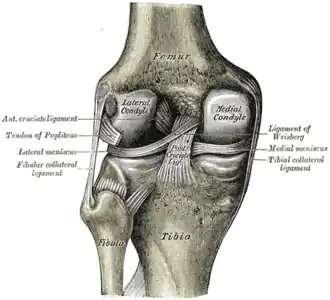

Left knee-joint from behind, showing interior ligaments. | |

The lateral condyle is one of the two projections on the lower extremity of the femur. The other one is the medial condyle. The lateral condyle is the more prominent and is broader both in its front-to-back and transverse diameters.